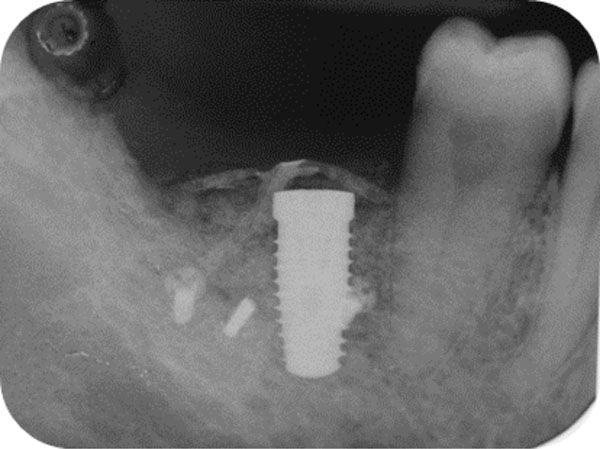

Post-surgical endoral x-ray showing the correct implant positioning and bone defect restoration.

Radiographic examination was performed to verify correct implant positioning and bone- defect restoration (Fig. 8). The patient was instructed to consume a soft diet and avoid mastication in the area of surgery for the first 6 weeks. In addition, he was told to rinse twice a day with 0.2% chlorhexidine mouthwash and avoid brushing the surgical site for the first 2 weeks. Amoxicillin 1 g every 8 hours was prescribed for 1 week and non-steroidal-anti-inflammatory (Aulin, Hoffmann-La Roche, Switzerland) drugs for 5 days.